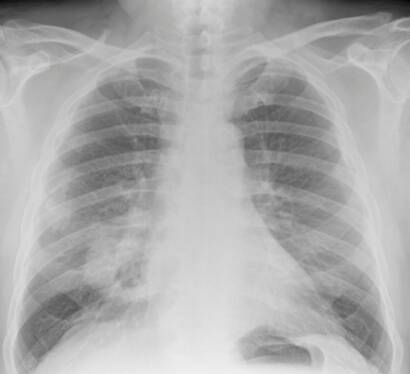

Los principales riesgos del amianto para la salud son: La asbestosis (fibrosis pulmonar), el cáncer de pulmón y el mesotelioma (pleural o peritoneal), habiéndose encontrado también asociación con otras neoplasias (carcinomas gastrointestinales o de laringe). Existe sospecha, no confirmada, de que el asbesto puede producir otros cánceres (riñón, ovario, mama).